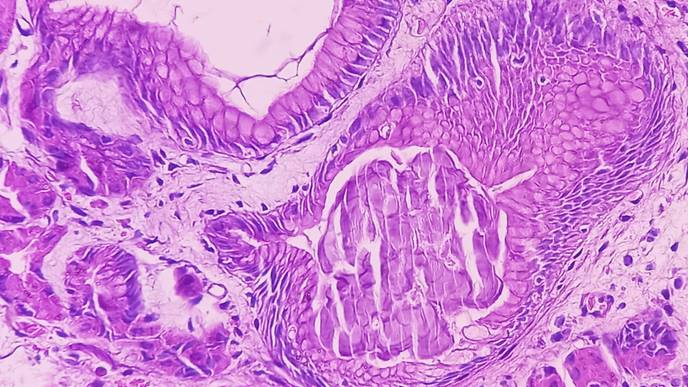

"The squamous epithelia of the esophagus and the columnar epithelia of the stomach meet at the gastroesophageal junction," explains Dr. Naveen Kumar Nirchal, one of the first authors of the study. The area is known as a "hotspot for the development of metaplasia" - the replacement of one type of cell by another.

Barrett's esophagus, a precursor to esophageal cancer, often develops there, the number of cases of which has increased dramatically in the Western world over the past four decades. "Barrett's esophagus is characterized by the replacement of the resident squamous epithelium of the esophagus by other cell types that are not normally found in this tissue," says the scientist.